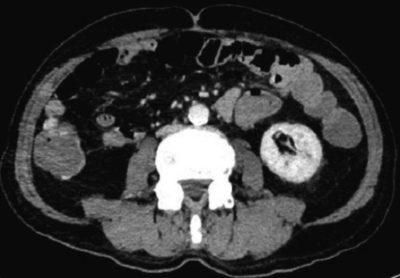

検査所見:血液所見:赤血球 299 万、Hb 9.7 g/dL、Ht 32 %、白血球 12,000、血小板 21 万。血液生化学所見:総蛋白 6.5 g/dL、アルブミン 3.6 g/dL、総ビリルビン 0.9 mg/dL、AST 28 U/L、ALT 22 U/L、LD 277 U/L (基準 176〜353)、γ-GTP 41 U/L (基準 8〜50)、アミラーゼ 80 U/L (基準 37〜160)、尿素窒素 18 mg/dL、クレアチニン 1.1 mg/dL、尿酸 6.7 mg/dL、血糖 128 mg/dL、Na 140 mEq/L、K 4.5 mEq/L、Cl 100 mEq/L。CRP 1.9 mg/dL。腹部単純 CT及び腹部造影 CTを別に示す。

腹部単純CT